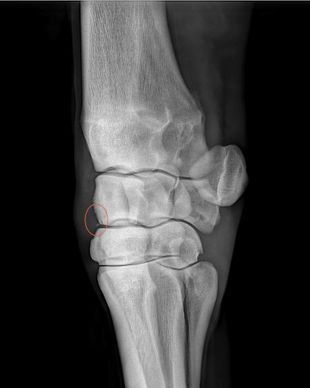

Digital radiography is used to view images of bone and soft tissue. The images are digital, rather than film and are available immediately, allowing for quick, on-site assessment of problems. The ability to manipulate the images on the computer and enhance specific regions of the image allows for better visualization of the problem areas.

Radiography is most commonly used in horses to view problems within the legs, making it an invaluable tool for lameness evaluations. Radiography is also very helpful in pre-purchase examinations, by helping uncover underlying or potential lameness issues before they manifest themselves symptomatically.